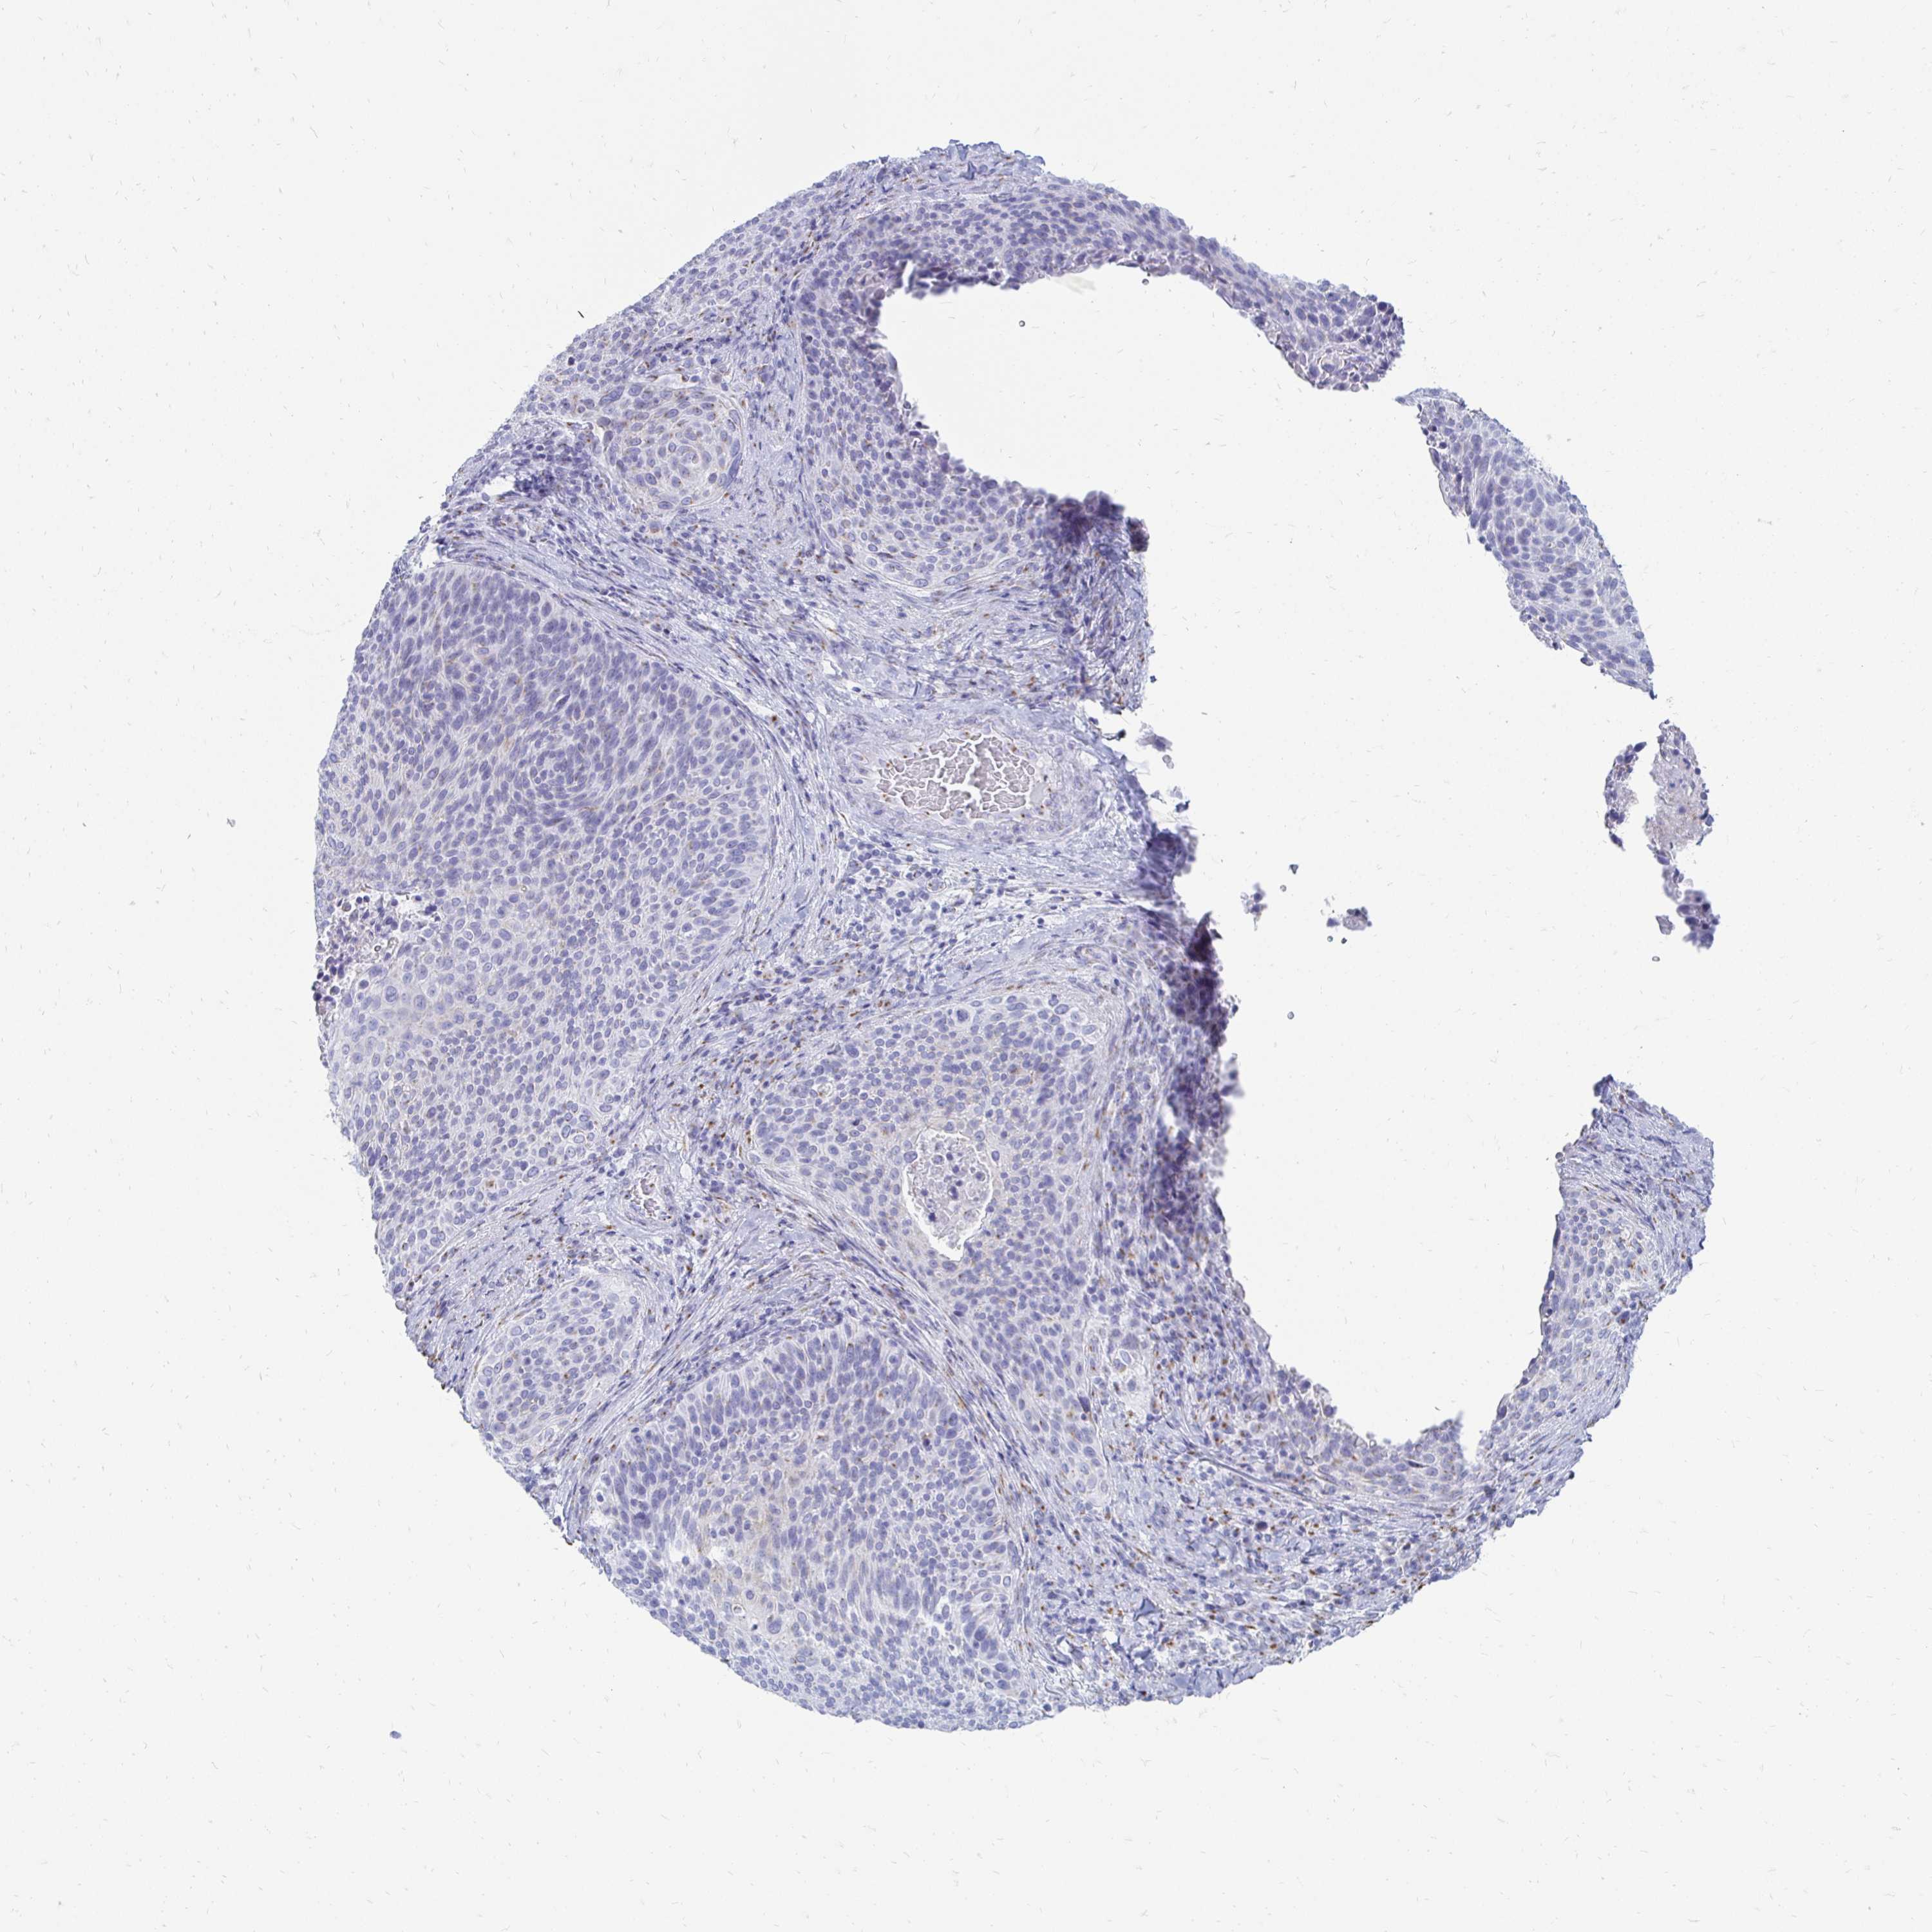

CERVICAL CANCER - Protein expressioni

A mouse-over function shows sample information and annotation data. Click on an image to view it in a full screen mode. Samples can be filtered based on level of antibody staining by selecting one or several of the following categories: high, medium, low and not detected. The assay and annotation is described here.

Note that samples used for immunohistochemistry by the Human Protein Atlas do not correspond to samples in the TCGA dataset.

Antibody stainingi

Antibody staining in the annotated cell types in the current human tissue is reported as not detected, low, medium, or high, based on conventional immunohistochemistry profiling in selected tissues. This score is based on the combination of the staining intensity and fraction of stained cells.

Each image is clickable and will lead to virtual microscopy that enables deeper exploration of all samples and also displays staining intensity scores, fraction scores and subcellular localization as well as patient and tissue information for each sample.

Antibody HPA023880

Staining

High

Medium

Low

Not detected

Intensity

Strong

Moderate

Weak

Negative

Quantity

>75%

75%-25%

<25%

None

Location

Nuclear

Cytoplasmic/membranous

Cytoplasmic/membranous,nuclear

Squamous cell carcinoma, NOS

Adenocarcinoma, NOS